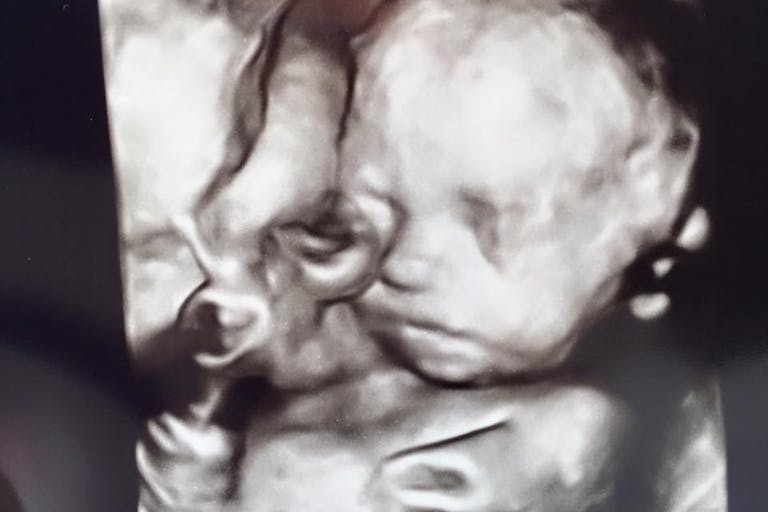

His little face was perfectly formed, just like the sign you saw, perfectly formed; little eyes were closed, little ears and everything was perfect about this little boy.